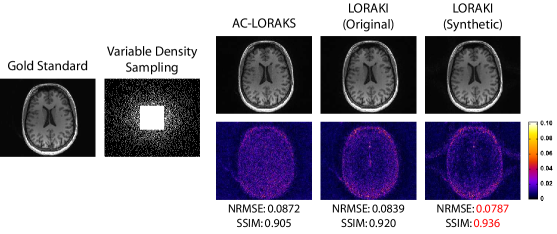

Figureย 3, Tableย 2, and supporting Fig.ย S1 show results from reconstructing randomly-undersampled T1-weighted data. In this specific case, we simulated an acquisition with an effective acceleration factor of (including samples from a fully-sampled ACS region at the center of k-space). Similar to the previous case, LORAKI had uniformly smaller NRMSE and larger SSIM values compared to AC-LORAKS, with the most significant error improvements at high spatial frequencies. GRAPPA and RAKI reconstruction were not performed in this case, due to the large number of local sampling configurations resulting from random sampling. As before, there was not a big difference between using the original ACS data versus using synthetic ACS data, which might be explained by the relatively large size of the acquired ACS data.